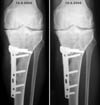

Die aktuellen Röntgenbilder (bitte klicken für grössere Fassungen):

Vergleich 15. August 2005 und 19. September 2005 von vorne